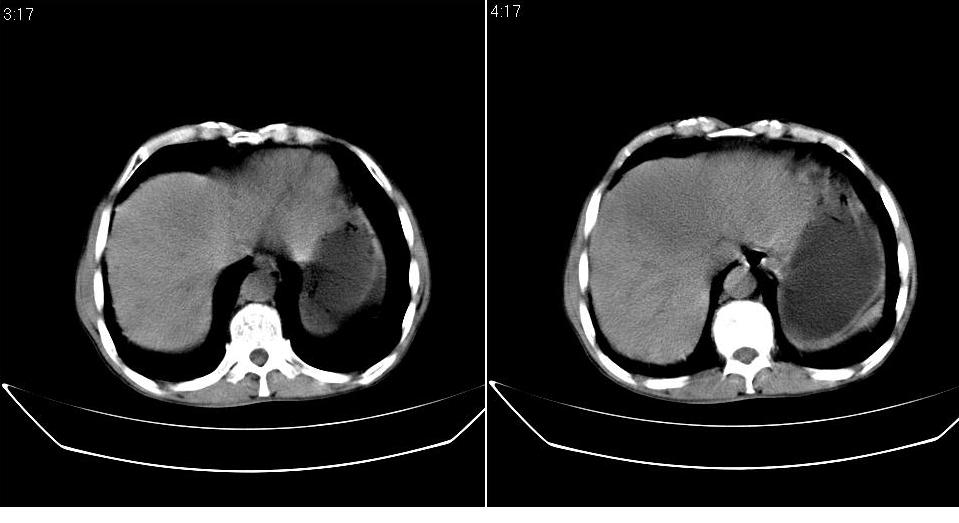

标题: CT20033:上腹部CT平扫

男 66岁,腹疼,b超提示考虑肝癌。

考虑巨块型型肝癌坏死、出血。建议增强。

考虑肝左叶巨块型肝癌可能性大;建议行增强ct扫描。

肝癌并门脉癌栓形成。